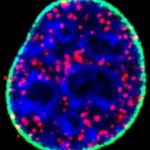

British researchers have discovered that an epigenetic protein called EZH2 delays the development of acute myeloid leukemia (AML) but then switches sides once...